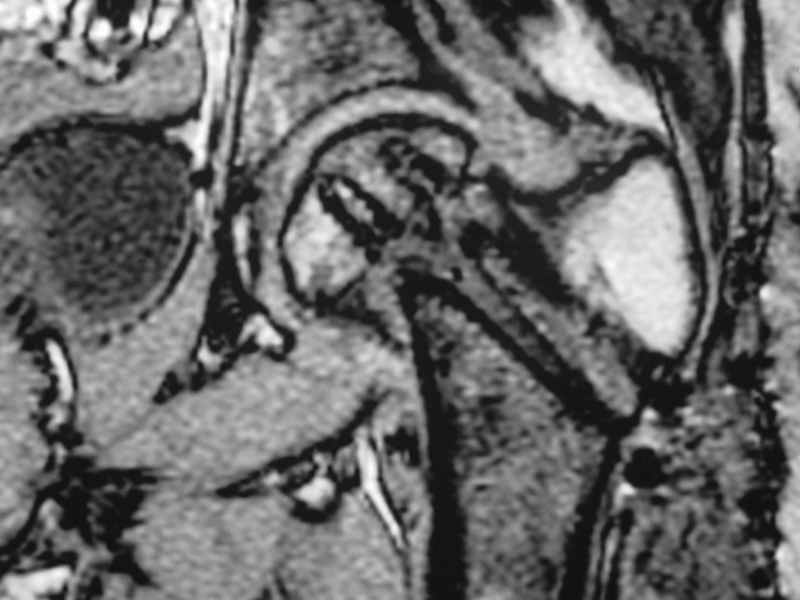

dhs will not correct improper biomechanical environment and may further compromise vascular

integrity consider establish vascular status via mri

and if viable follow with proximal valgus osteotomy